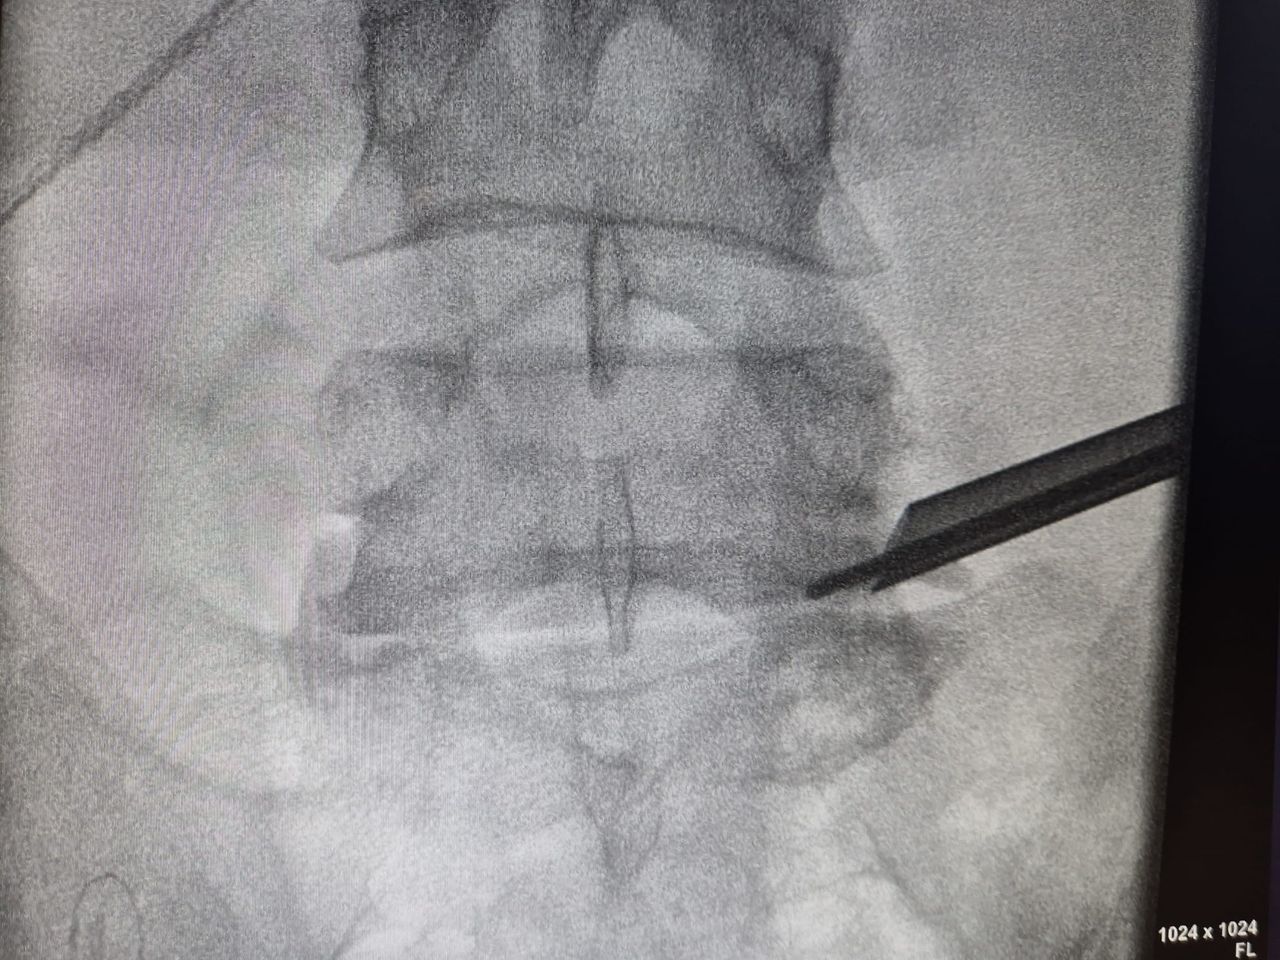

Starszy Asystent w Klinicznym Oddziale Neurochirurgicznym oraz Poradni Neurochirurgii Wojewódzkiego Szpitala Specjalistycznego im. św. Barbary nr 5 w Sosnowcu. Konsultant Kliniki Neurologii Szpitala Klinicznego nr 1 w Zabrzu. Absolwent Wydziału Lekarskiego Śląskiego Uniwersytetu Medycznego w Zabrzu. Staż podyplomowy odbył w latach 2010-2011 w Oddziale Neurochirurgii WSS nr 4 w Bytomiu. W 2018r. złożył egzamin specjalizacyjny po zakończeniu szkolenia w ramach rezydentury w WCM Opole. W 2019 roku uzyskał stopień doktora nauk medycznych. Specjalizuje się w kompleksowym leczeniu schorzeń kręgosłupa (dyskopatia, stenoza kanału kręgowego, kręgozmyk) oraz neuroonkologii. Szczególny zakres działań medycznych to nowoczesne, małoinwazyjne operacje kręgosłupa z wykorzystaniem technik endoskopowych (mikrodiscektomia - implanty rozprężalne), przezskórnych stabilizacji oraz mikrochirurgicznych dekompresji. Wykonuje procedury iniekcyjne; discoGEL, GelSTIX, kriolezje oraz blokady przeciwbólowe kręgosłupa odcinka szyjnego, lędźwiowo-krzyżowego a także stawów krzyżowo-biodrowych, które odgrywają istotną rolę w procesie diagnostyczno-leczniczym wielu zespołów bólowych. Na co dzień przeprowadza operacje w ramach kontraktu z NFZ. Członek Polskiego Towarzystwa Neurochirurgów oraz Polskiego Towarzystwa Chirurgii Kręgosłupa. Uczestnik wielu krajowych i zagranicznych kursów neurochirurgicznych, m.in. w Czechach, Słowacji, Niemczech, Włoszech, Danii, Austrii, Szwajcarii i USA. Autor licznych publikacji naukowych.

Zdjęcia i filmy